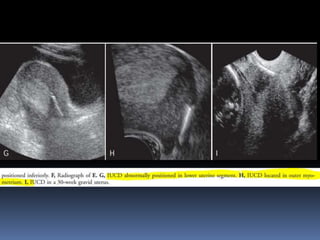

This document contains an image gallery from Dr. Mohit Goel showing various uterine anomalies and ovarian cysts. It includes images of an arcuate and unicornuate uterus, endometritis, a twisted ovarian pedicle, dermoid cysts of varying sizes and echogenicity containing hair, fat, and calcifications, and a combination dermoid cyst showing both mesh and plug structures. The gallery provides ultrasound images of different gynecological conditions for medical education and reference.